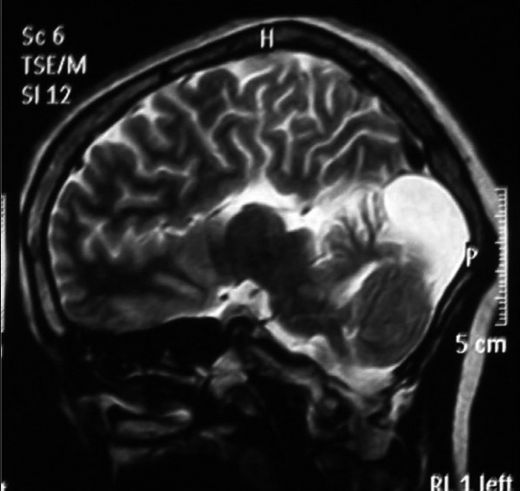

Dandy Walker sendromu, doğuştan gelen bir beyin anomalisidir ve genellikle beyincik ile ilgili yapısal bozuklukları ifade eder. Bu sendrom, beyincik kistleri, genişlemiş arka kafa bölgesi ve bazen de beyincik loblarının anormal gelişimi ile karakterizedir. Dandy Walker sendromu, çeşitli nörolojik ve fiziksel semptomlara yol açabilir. Dandy Walker Sendromunun Belirtileri Dandy Walker sendromunun belirtileri bireyler arasında değişiklik gösterebilir. Ancak, en yaygın olarak görülen belirtiler şunlardır: